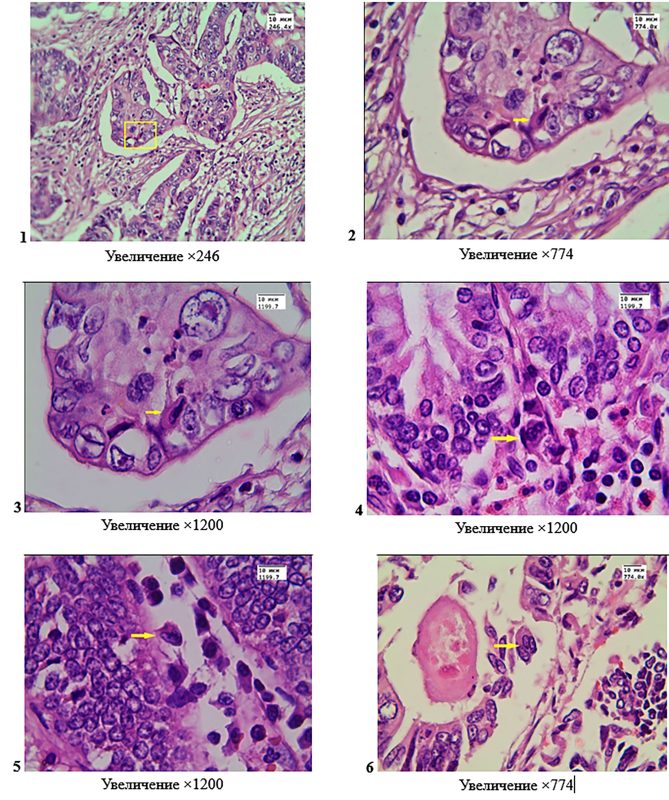

Операционные препараты резецированных сегментов толстой кишки по поводу опухолей, имеющих строение умеренно дифференцированной аденокарциномы, окраска гематоксилином-эозином. Фото 1, 2, 3 – двухъядерная клетка (показана квадратом и стрелками) с двумя фенотипически разными ядрами, одно из них гиперхромное; клетка имеет морфологические признаки гетерокариона гибридного происхождения; клетка располагается среди эпителиоцитов опухолевой ткани. Фото 4, 5, 6 – среди крипт имеются многоядерные клетки (показаны стрелками), ядра которых фенотипически схожи с ядрами эпителиоцитов; клетки не связаны с базальной мембраной; на фото 6 – клетка, в которой отчетливо видны 3 ядра, вследствие слияния эпителиоцитов, что указывает на её гибридное происхождение